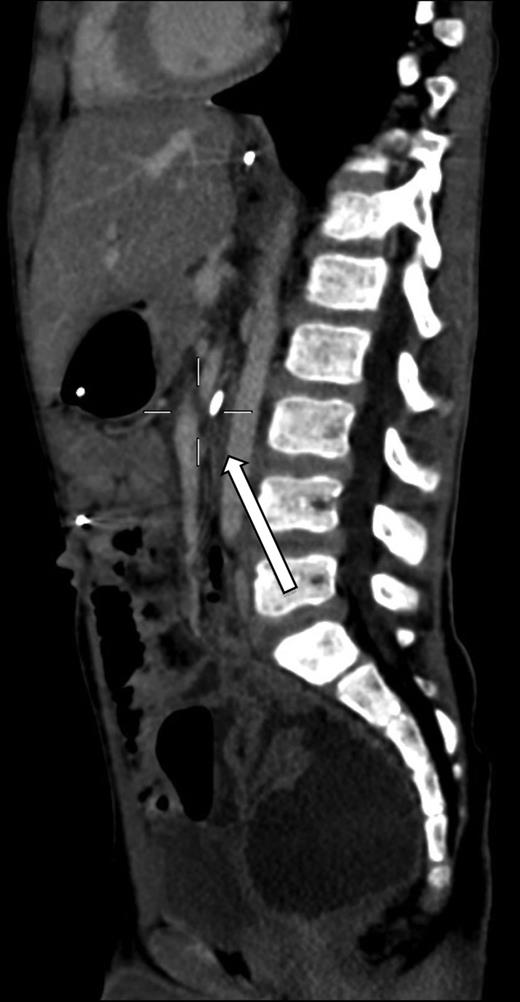

A 7-year-old boy who had been treated at 3 years of age for a subtotal colonic Hirschsprung disease with a Deloyers’ procedure was admitted for persistent bilious vomit associated with recurrent episodes of postprandial abdominal pain and diarrhea. The parents reported a progressive weight loss of 3.5 kg during the last 3 years. The patient was emaciated with severe chronic malnutrition; the weight and the length were 15.19 kg and 113 cm [body mass index (BMI): 11.9 kg/m2], both between the third and the fifth percentile, respectively. The clinical abdominal examination was normal. A plain abdominal X-ray showed a distended stomach with paucity of gas in the distal bowel. An abdominal ultrasound confirmed a dilated duodenum without signs of mechanical obstruction of the small bowel and a normal relationship between the superior mesenteric vessels. An upper gastrointestinal contrast study confirmed dilatation of the first and second portions of the duodenum with little progression of contrast medium across the third portion released in left lateral position (Fig. 1). An SMAS was confirmed by a computed tomography (CT) scan that showed a reduction in retroperitoneal preduodenal and mesenteric fat and compression of the third duodenum by the superior mesenteric artery with an acute 13° angle and a 7.5 mm distance from the aorta (Fig. 2). A gastrointestinal endoscopy confirmed the dilatation of the duodenum with an inflammatory mucosa and a normal jejunum. Gastric and duodenal biopsies were performed and a nasojejunal tube was guided through the duodenum to the Treitz to start enteral feeding (Fig. 3).

The upper gastrointestinal contrast study shows poor progression of contrast medium across duodenal obstruction. Arrow shows obstruction of the third duodenum.